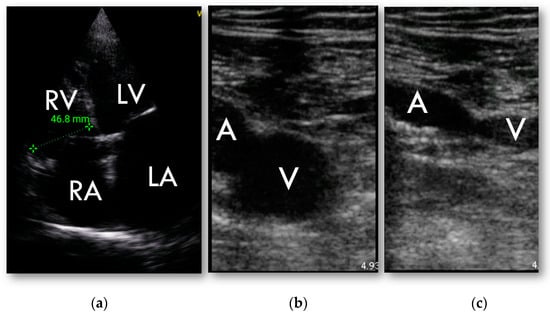

Lung lesions typical for COVID-19 were confirmed in CT in 53 (84%) patients (Figure 1). Ground glass opacities were present in 50 patients, pleural thickening in 21 patients and subpleural consolidation in 28 patients. Lung abnormalities were detected in HUD examination in 50 patients (>3 B-lines in 43 patients, thickened pleural line in 25 patients and subpleural consolidation in 25 patients) (Figure 1). The sensitivity and specificity of bedside HUD examination for diagnosing lung involvement was 92% and 90% retrospectively, AUC = 0.92, p < 0.0001. Weighted Cohen’s kappa was 0.735 (± 0.111, 95% CI 0.517–0.953). The highest concordance with CT was found for pleural thickening (kappa 0.788 ± 0.07, 95% CI 0.651–0.926). The detailed comparisons of bedside HUD examination and CT for diagnosing lung involvement are presented in Table 2.

Figure 1.

Examples of lung ultrasonography performed with HUD. (a) increased number of B-lines; (b) pleural thickening; (c) subpleural consolidation (abnormalities marked with arrows).